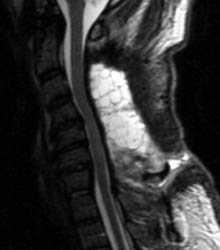

46 y.o.  male, initial complaint of progressed with myelopathy, difficulty walking, and imbalance. Underwent laminectomy C3 to C7, 2 months prior to these images. Worsening numbness and weakness brought patient to seek neurosurgical consultation again, prompting repeat imaging.

Sagittal T1 pre (A) and post contrast (B),  sagittal T2 (C) and Axial T1 post contrast (D) MRI images of the cervical spine demonstrating a large posterior fluid collection with an obvious sinus tract inferiorly and associated gas bubbles. This was proved to be a post-operative seroma and epidural scar (note the thick rind of enhancement) that was partially accounting for this patient's residual and worsening symptoms despite the initial decompressive surgery.